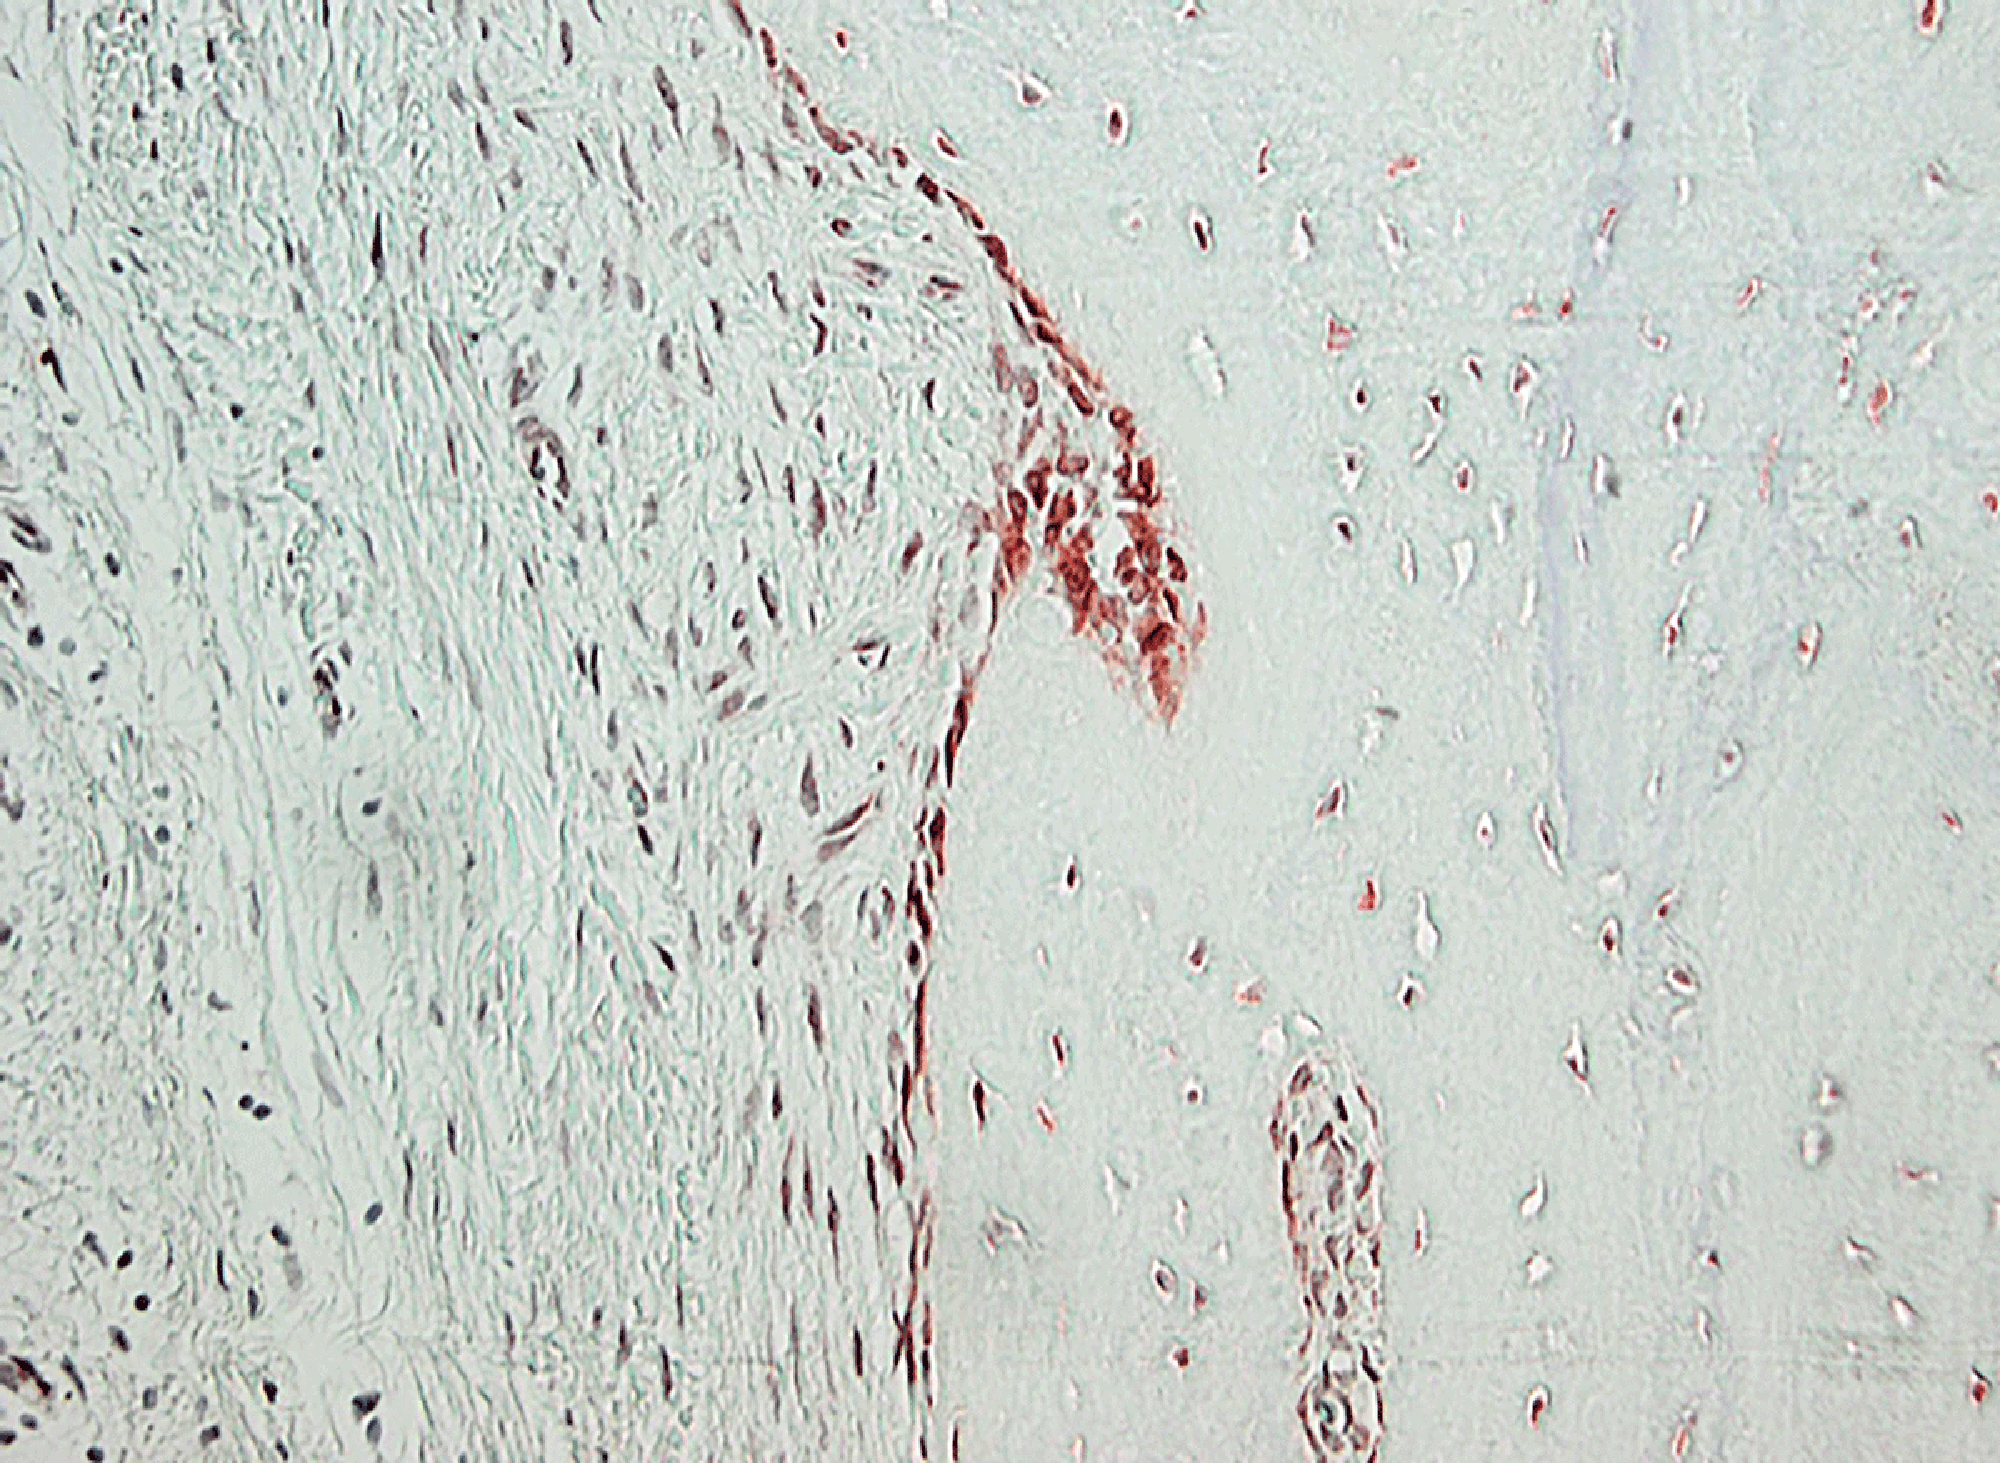

Zusätzlich tragen Immunzellen und andere Zellen im Körper Moleküle auf ihrer Oberfläche, an die Dopamin andocken und somit Signale übermitteln kann. Diese Dopamin-Rezeptoren konnten beispielsweise in Gelenkzellen von Personen mit rheumatoider Arthritis (RA) nachgewiesen werden.